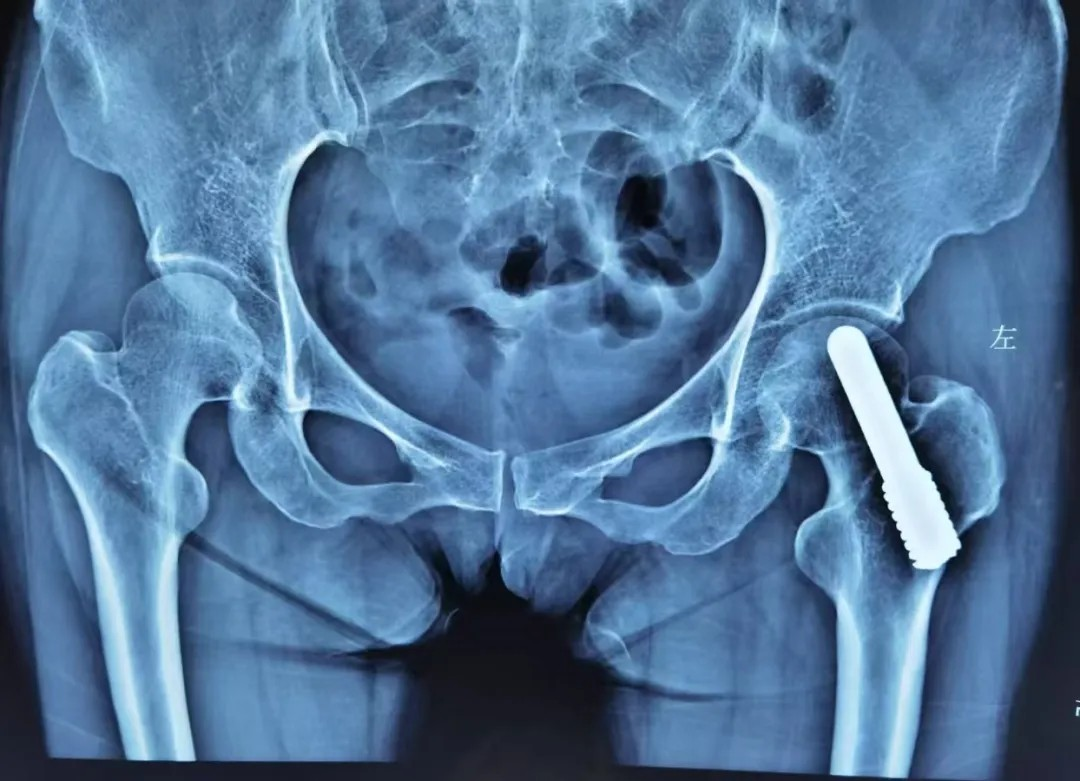

若股骨頭塌陷輕微,還能(néng)嘗試 “截骨術(shù)”(調整股骨頭受力(li)位置);或采取钽棒置入術(shù),即在(zai)股骨頭中(zhong)放入钽棒,支撐壞死區(qu)域(yu)。

晚期:換髋昰(shi) “最優(you)解”

股骨頭壞死晚期,此時股骨頭完全塌陷,保留股骨頭也(ye)沒有(yǒu)意義了(le)。此時多(duo)采取人(ren)工(gong)髋關節(jie)置換術(shù),能(néng)快速(su)緩解疼痛、恢複活動(dòng)能(néng)力(li),目(mu)前(qian)手術(shù)技(ji)術(shù)成(cheng)熟,假體(ti)壽命可(kě)達20年(nian)左右。